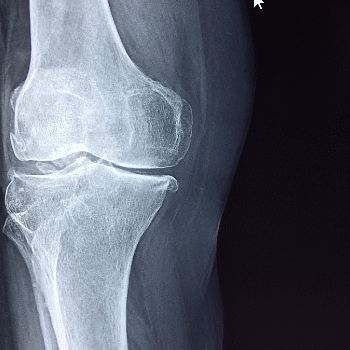

콘드로이친 효능 1. 관절 연골 보호 및 재생

콘드로이친은 관절의 연골을 보호하고 재생을 촉진하는 데 중요한 역할을 합니다. 연골은 관절에서 뼈와 뼈 사이를 부드럽게 움직이도록 돕는 쿠션 역할을 하는 조직입니다. 콘드로이친은 연골 세포를 보호하고, 외부 충격으로부터 연골을 보호하며, 세포외기질의 주요 성분으로서 연골의 구조와 기능을 유지합니다. 이를 통해 관절염 환자의 연골 손상을 줄이고, 새로운 연골 세포의 형성을 촉진하여 관절 건강을 개선합니다.

콘드로이친 효능 2. 관절염 증상 완화

콘드로이친은 골관절염과 같은 관절염 질환의 증상을 완화하는 데 효과적입니다. 연구에 따르면, 콘드로이친은 통증과 염증을 줄이고, 관절 기능을 개선하여 삶의 질을 높이는 데 도움을 줍니다. 관절염 환자는 종종 관절 부위의 통증과 뻣뻣함을 겪으며, 콘드로이친은 이러한 증상을 경감시켜 보다 자유로운 움직임을 가능하게 합니다.